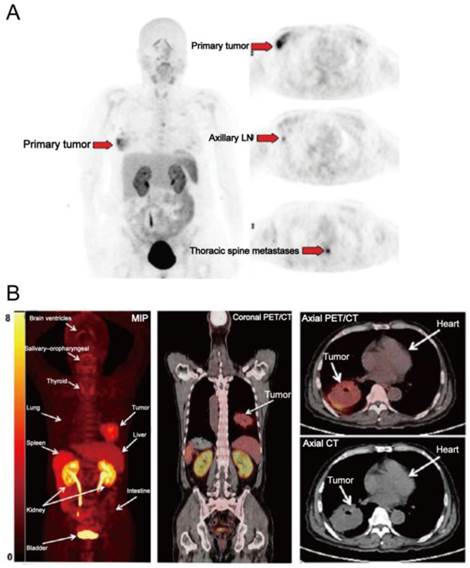

Figure 4

(A) [18F]FPPRGD2 PET images in a patient with multicentric lobular carcinoma of the right breast. [18F]FPPRGD2 PET image shows the primary right breast lesion, right axillary lymph node, and thoracic spine metastases (arrows; all proven by biopsy). (B) [18F]Alfatide PET images in a patient with non-small cell lung cancer. Major organs and regions are labeled with arrows. Corresponding PET/CT fusion image at certain coronal slice further shows uptake of tumor and other organs. Reproduced with permission from references [65][26].

[18F]FPPRGD2 was the first dimeric RGD peptide tracer applied in the clinic for PET imaging [64]. In a clinical study with 8 breast cancer participants [65], primary and metastatic lesions showed [18F]FPPRGD2 uptake with SUVs of 2.4-9.4 (mean, 5.6 ± 2.8) and 2.5-9.7 (mean, 5.0 ± 2.3) at 60 min p.i. (Figure 4A). No significant difference in SUVs was found between [18F]FPPRGD2 and [18F]FDG PET, for both primary lesions and metastases. Similar results were also reported in a recent study which compared [18F]FPPRGD2 with [18F]FDG PET in 35 patients [38]. The average tumor SUVs from [18F]FPPRGD2 PET is higher than those from [18F]Galacto-RGD and [18F]Fluciclatide PET, which is in accord with the preclinical animal studies [22]. Interestingly, in the case of lobular breast cancer, there was obvious tracer uptake in primary lesion and in sub-centimeter biopsy-proven axillary lymph nodes and thoracic spine metastases, whereas these lesions were not detected by 18F-FDG PET. Furthermore, three biopsy-proven inflammatory lymph nodes showed mild 18F-FDG uptake but no [18F]FPPRGD2 accumulation. Therefore, the overall sensitivity and specificity of [18F]FPPRGD2 PET (95.7% and 100%, respectively) were higher than those of [18F]FDG PET (87.0% and 57.1%, respectively). In a more recent study, [18F]FPPRGD2 PET was performed in 15 patients with recurrent GBM, and compared with [18F]FDG and brain MR. Surprisingly, [18F]FPPRGD2 PET showed a higher detection rate of recurrent GBM than brain MR (100.0% vs. 93.3%) and [18F]FDG (100.0% vs. 86.7%) [41]. With regard to another dimeric RGD peptide [18F]Alfatide, one clinical study investigated the feasibility of [18F]Alfatide PET for lung cancer detection (Figure 4B). Results showed that [18F]Alfatide PET was able to clearly identify all primary lesions (sensitivity is 100% for primary lesions) with desirable image contrast (mean tumor SUV, 2.9±1.0) [26]. In order to evaluate the diagnostic value of dimeric RGD in metastatic lesions, [18F]Alfatide II PET was recently performed in patients with bone metastases [66] and brain metastases [35], respectively. For bone metastasis from 30 patients, [18F]Alfatide II PET/CT has similar detection efficiency as [18F]FDG PET/CT for detecting osteolytic and mixed bone metastases (100% vs. 90%). However, [18F]Alfatide II is superior to [18F]FDG for osteoblastic lesions (70% vs. 53%) (Figure 5). For bone marrow metastatic lesions, the positive rate of [18F]Alfatide II PET was also higher than that of [18F]FDG PET (98% vs. 77%). In all bone metastatic lesions, no significant difference of tracer uptake was observed between [18F]Alfatide II and [18F]FDG (4.27 ± 2.42 vs. 4.18 ± 2.58, P > 0.05). For brain metastases, all 20 brain lesions from 9 patients were visualized by [18F]Alfatide II PET, while only 10 by [18F]FDG PET, and 13 by CT. Despite the fact of overall higher tumor uptake of [18F]FDG over [18F]Alfatide II (10.0 ± 5.7 vs. 1.8 ± 1.1), [18F]Alfatide II demonstrated much higher tumor/background ratio (18.9 ± 14.1) than [18F]FDG (1.5 ± 0.5), which is consistent with the clinical data from [18F]FPPRGD2 study [41].